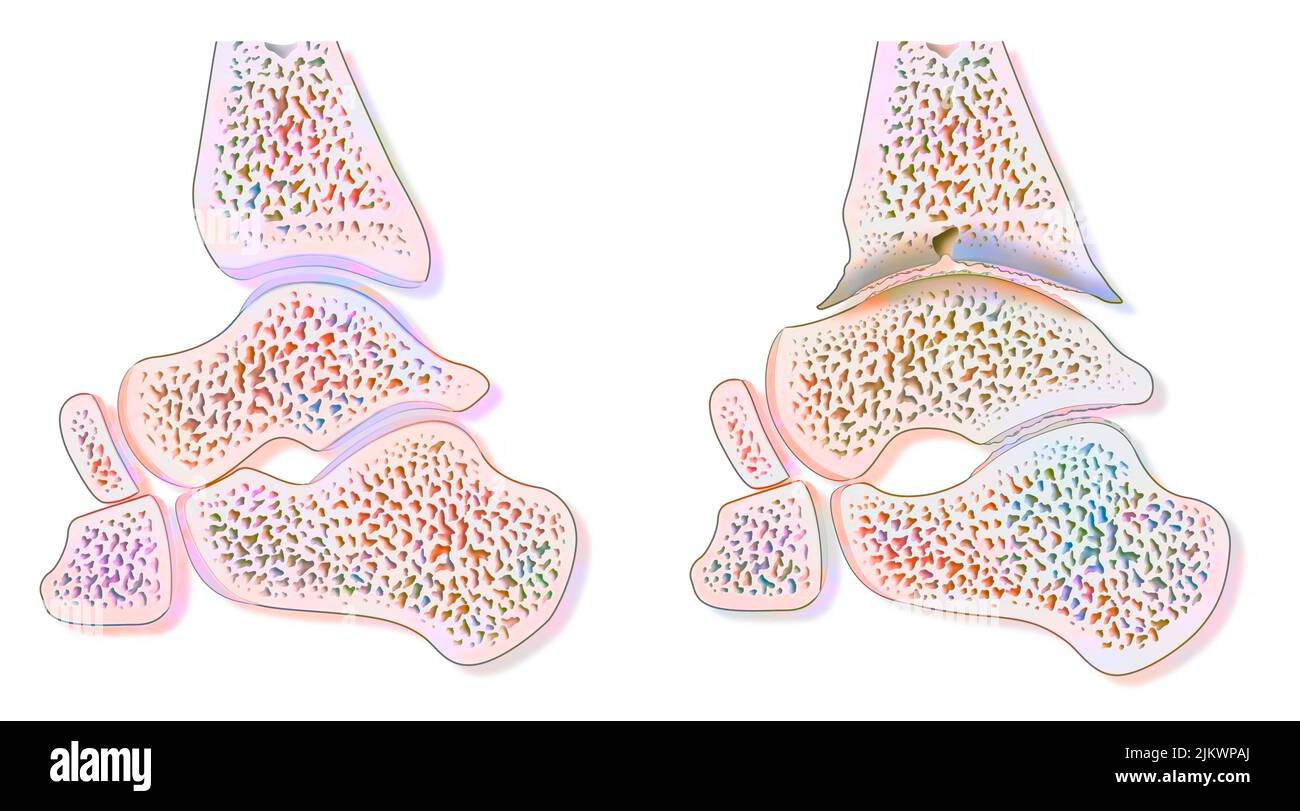

RF2K3D0JE–Illustration du rendu de l'hallux valgus ou du bunion x-ray 3D. Vue dorsale ou de dessus du pied gauche en bonne santé et blessé sur fond bleu. Anatomie, ostéol

RF2K3D0JF–Illustration du rendu de l'hallux valgus ou du Boignon 3D. Vue supérieure ou dorsale des os du pied gauche humains avec contours du corps sur fond bleu. Un